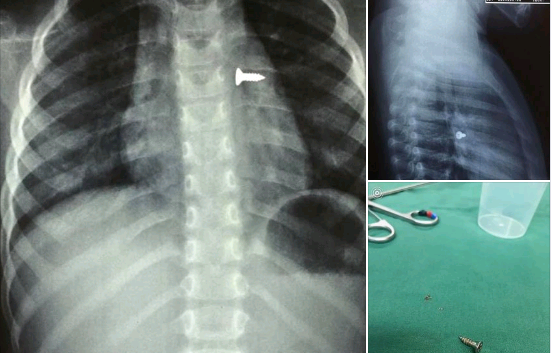

Ώρες αγωνίας έζησε την Τρίτη (1/12) η οικογένειά ενός 3χρονου κοριτσιού στο Ηράκλειο όταν κάτω από αδιευκρίνιστες συνθήκες, το παιδάκι κατάπιε μία βίδα.

Διεκομίσθη άμεσα στο νοσοκομείο με τους γιατρούς να το βάζουν απευθείας στο χειρουργείο προκειμένου να του αφαιρέσουν το αντικείμενο το οποίο στάθηκε στον αριστερό πνεύμονά του.

Σύμφωνα με τον αναπληρωτής καθηγητής ΩΡΛ της Ιατρικής Σχολής Κρήτης, Μανώλη Προκοπάκη, επρόκειται για ένα πολύ επικίνδυνο συμβάν που θα μπορούσε εύκολα να βάλει σε κίνδυνο τη ζωή του κοριτσιού.